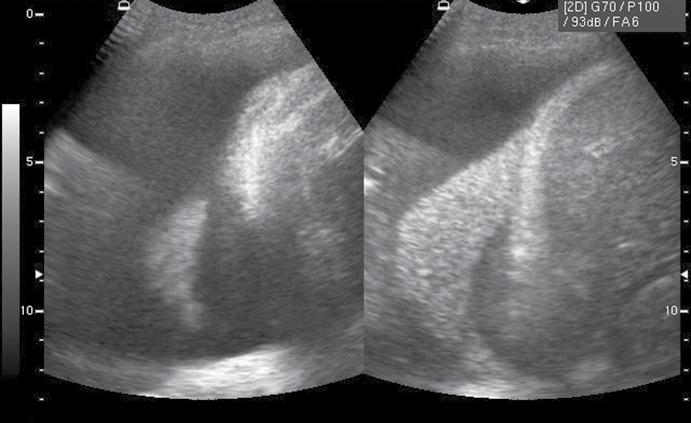

▶ Introducerea algoritmului de investigare a pacientului cu hipotensiune/ șoc RUSH (PUMP-TANK-PIPE) după cum urmează și luarea unor decizii bazate pe evidențe suport: o cordul („PUMP“)

• contractilitatea globală a ventriculului stâng, identificând mărimea și statusul contractil – prezența unei insuficiențe cardiace acute (fig.2) cu necesitatea administrării medicației diuretice, inotrope, vasoactive în funcție de parametrii hemodinamici și corelarea cu aspectul plămânului și a venei cave; vizualizarea unui ventricul stâng hiperkinetic, cu reducerea volumui cavității (fig.3) ceea ce indică corelat cu aspectul VCI cu diametru redus (fig.4) o stare de hipovolemie ce necesită administrarea de fluide;

• aprecierea mărimii ventriculului stâng comparativ cu cel drept – identificarea unei supraîncărcări a ventriculului drept, cu suspiciunea de cord pulmonar acut (fig.5) și necesitatea de administrare de trombolitic pentru trombembolism pulmonar;

Fig.4. Secțiune intercostală dr. venă cavă inferioară

Fig.5. Secțiune subxifoidiană. Cord drept dilatat

Fig.6. Secțiune intercostală dreaptă. Colecție pleurală masivă. Atelectazie pulmonară de compresiune